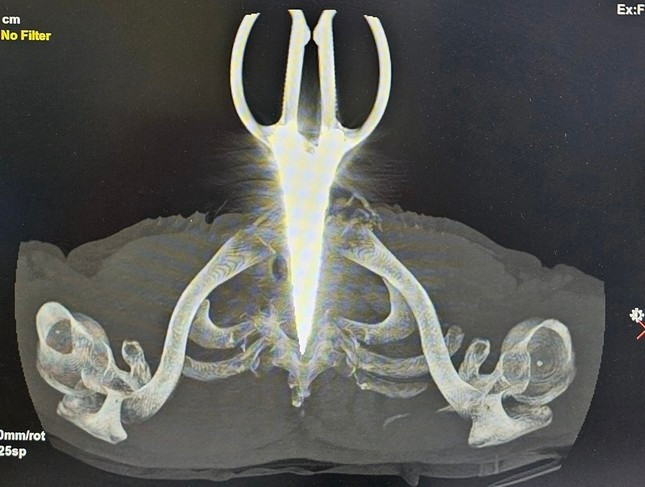

Ảnh phim X-Quang cây kéo dài 24cm đâm cổ bệnh nhân.

Kết quả X-Quang và chụp cắt lớp vi tính ghi nhận, dị vật kim loại xuyên giữa cột sống ngực D1 của anh H. Sau hơn 2 giờ phẫu thuật, chiếc kéo đã được lấy thành công khỏi người anh H., cùng với việc xử lý các tổn thương khác của bệnh nhân.